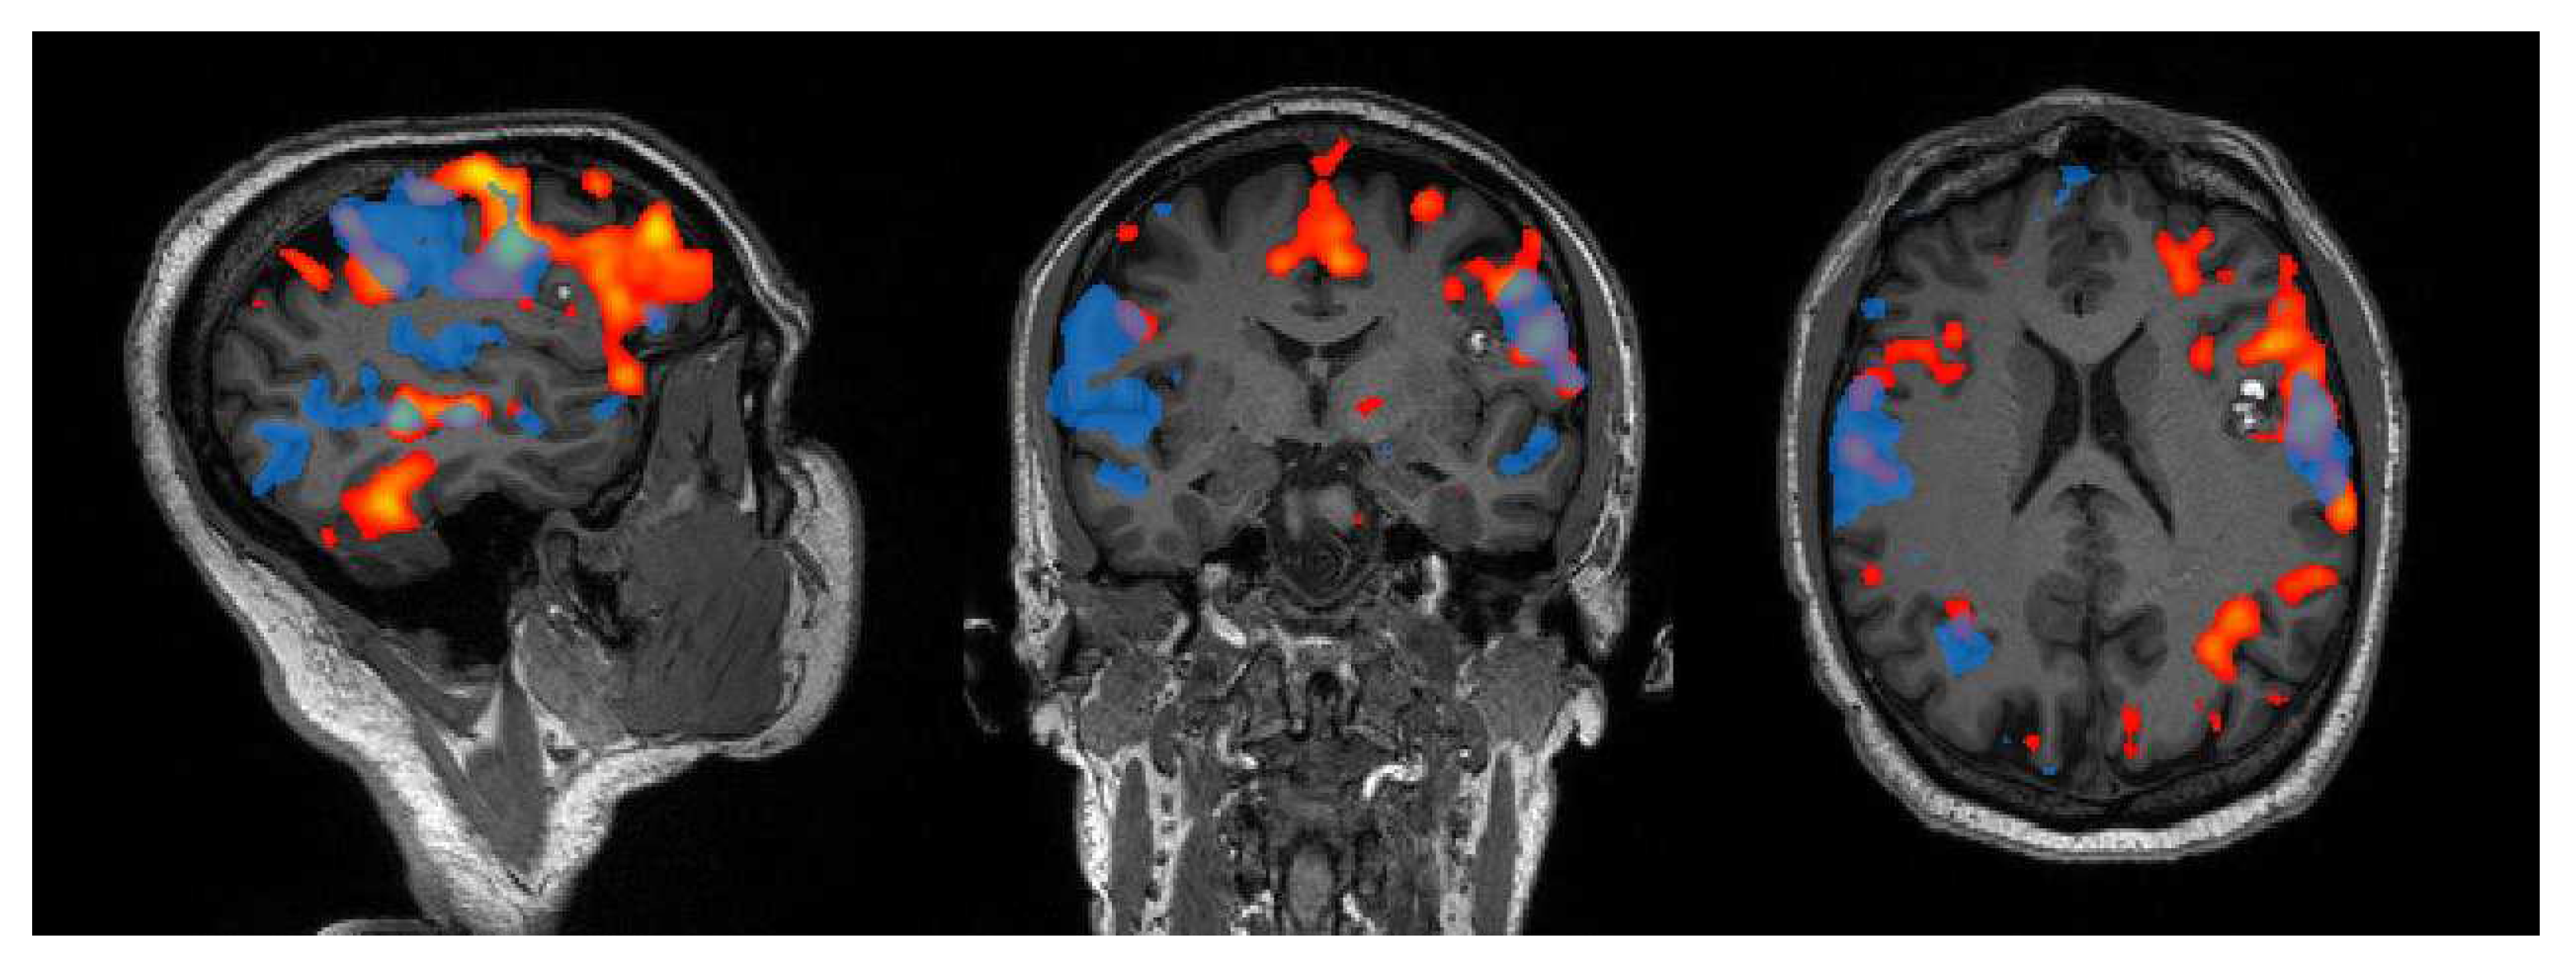

What Can Resting-State fMRI Data Analysis Explain about the Functional Brain Connectivity in Glioma Patients?

Sighinolfi, G.; Mitolo, M.; Testa, C.; Martinoni, M.; Evangelisti, S.; Rochat, M.J.; Zoli, M.; Mazzatenta, D.; Lodi, R.; Tonon, C. What Can Resting-State fMRI Data Analysis Explain about the Functional Brain Connectivity in Glioma Patients? Tomography 2022, 8, 267-280. https://doi.org/10.3390/tomography8010021